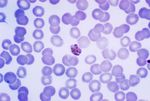

| Taxonomy: | Eukaryota | Opisthokonta | Fungi | Dikarya | Ascomycota | saccharomyceta | Pezizomycotina | leotiomyceta | Eurotiomycetes | Eurotiomycetidae | Onygenales | Onygenales incertae sedis | Paracoccidioides | Paracoccidioides lutzii |

| Synonym: | Paracoccidioides sp. 'lutzii' Pb01, Loboa loboi, Aleurisma brasiliensis (obsolete), Blastomyces brasiliensis (obsolete), Coccidioides brasiliensis (obsolete), Coccidioides histosporocellularis (obsolete), Lutziomyces histosporocellularis (obsolete), Monilia brasiliensis (obsolete), Mycoderma brasiliensis (obsolete), Mycoderma histosporocellularis (obsolete), Zymonema brasiliense (obsolete) |

| Comment: | Paracoccidioides brasiliensisis dimorphic and the causative agent for paracoccidioidomycosis, a chronic granulomatous disease of mucous membranes, skin, and pulmonary system. In contrast to the other yeasts, particularly Blastomyces, Paracoccidioides has multiple buds, a thin cell wall, and a narrow base. |

| Taxonomy: | Eukaryota | Opisthokonta | Fungi | Dikarya | Ascomycota | saccharomyceta | Pezizomycotina | leotiomyceta | Eurotiomycetes | Eurotiomycetidae | Onygenales | Onygenales incertae sedis | Paracoccidioides | Paracoccidioides brasiliensis |

| Synonym: | Loboa loboi, Aleurisma brasiliensis (obsolete), Blastomyces brasiliensis (obsolete), Coccidioides brasiliensis (obsolete), Coccidioides histosporocellularis (obsolete), Lutziomyces histosporocellularis (obsolete), Monilia brasiliensis (obsolete), Mycoderma brasiliensis (obsolete), Mycoderma histosporocellularis (obsolete), Zymonema brasiliense (obsolete) |

| Comment: | Paracoccidioides brasiliensisis dimorphic and the causative agent for paracoccidioidomycosis, a chronic granulomatous disease of mucous membranes, skin, and pulmonary system. In contrast to the other yeasts, particularly Blastomyces, Paracoccidioides has multiple buds, a thin cell wall, and a narrow base. |

| Taxonomy: | Eukaryota | Opisthokonta | Fungi | Dikarya | Ascomycota | saccharomyceta | Pezizomycotina | leotiomyceta | Eurotiomycetes | Eurotiomycetidae | Onygenales | Onygenales incertae sedis | Paracoccidioides | Paracoccidioides brasiliensis |

| Synonym: | Loboa loboi, Aleurisma brasiliensis (obsolete), Blastomyces brasiliensis (obsolete), Coccidioides brasiliensis (obsolete), Coccidioides histosporocellularis (obsolete), Lutziomyces histosporocellularis (obsolete), Monilia brasiliensis (obsolete), Mycoderma brasiliensis (obsolete), Mycoderma histosporocellularis (obsolete), Zymonema brasiliense (obsolete) |

| Comment: | Paracoccidioides brasiliensisis dimorphic and the causative agent for paracoccidioidomycosis, a chronic granulomatous disease of mucous membranes, skin, and pulmonary system. In contrast to the other yeasts, particularly Blastomyces, Paracoccidioides has multiple buds, a thin cell wall, and a narrow base. |